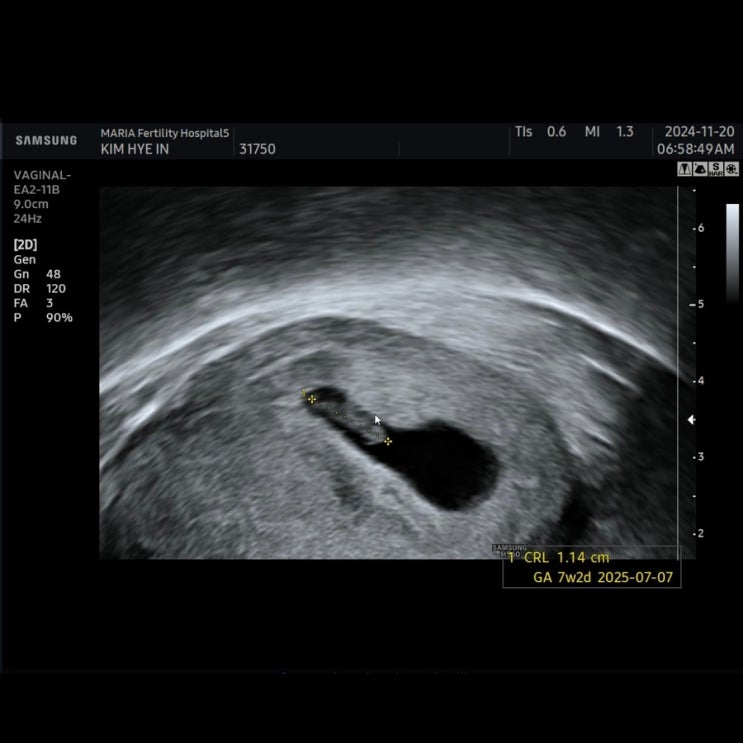

임신 7주차 / 임산부 독감주사, 단축근무 시작!

7주 0일 / 심장소리 듣는날 ∨ 속이 조금 더 안좋아진것 같은건 기분탓? ∨ 역시나 '라면' 생각...